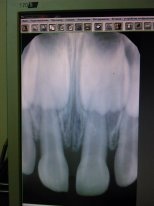

Здравствуйте! 10 дней назад ребенок упал и ударился зубом об пол, через 3-4 дня зуб почернел. Ребенку 3,5 г. Врач сказала, что при лечении можно задеть коренной зуб и он никогда не вырастет, лучше вырывать, а потом сказала, что аккуратно залечит без гарантии. Я в растерянности. Не хочется, чтобы ребенок до школы ходил беззубый и шипилявил и страшно повредить коренной. Если вырвать, не будут ли соседние зубы смещаться на место вырванного? Зуб у него не болит. Что делать? Какие могут быть последствия, если не лечить и не вырывать, так оставить? Нерв молочного зуба заходит на коренной и его могут повредить как при удалении, так и при лечении, но так же он может сгнить и повредить коренной зуб, может развиться флюс (мнение одного доктора)

Здравствуйте.Во-первых, не торопиться с вывода. Это пока может быть гематома.Через месяц нужно сделать повторный снимок.Если нерв погиб, оставлять в таком виде ситуацию нельзя- это может повредить зачаток постоянного зуба.Но удалять зуб НЕЛЬЗЯ! перелома-то никакого нет.И вылечить его реально, не травмируя зачаток постоянного зуба,т.к. в 3,5 года они еще находятся вне зоны доступа "случайным инструментом".Удалить из зуба погибший нерв и запломбировать канал... И все) И все будут довольны)Тому есть мнооооого примеров!